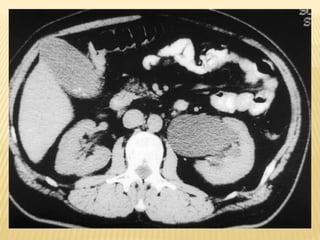

COMPUTED TOMOGRAPHIC SCAN (CT)

- It is an alternative to ultrasonography in the

symptomatic child.

-It is not the preferred modality due to its

radiation exposure.

- In UPJ obstruction, the CT scan typically

shows hydronephrosis without a dilated

ureter.